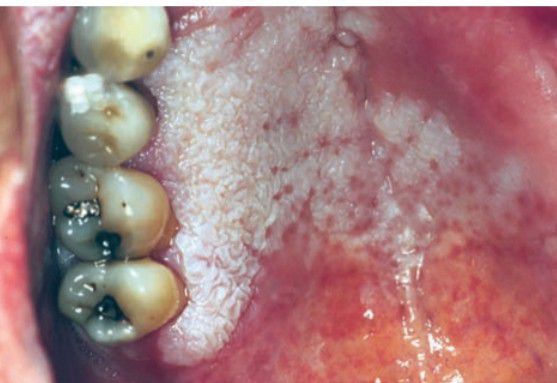

Proliferative verrucous leukoplakia

This type of leukoplakia, often on the gingiva, begins as simple keratosis and eventually becomes verrucous in nature.